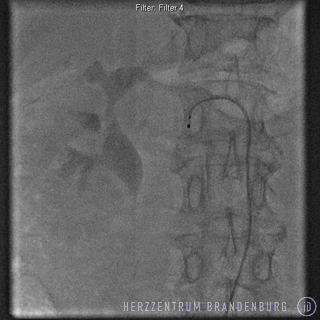

The procedure takes approximately 40 - 60 minutes. The catheter is introduced via a blood vessel in the groin, and is advanced to the renal artery. In order to ensure that the procedure does not cause any pain to the patient, a local aesthetic is applied to the groin area. Although there is no need for general anesthesia,

both sedatives and analgesics are administered throughout the procedure in order to ensure that the patient remains comfortable.

A special catheter is used to deliver radiofrequency pulses to different sites along the renal artery, with each radiofrequency pulse lasting approximately 2 minutes.

Both renal arteries are treated in this manner and, depending on the patient's anatomy, the entire process will usually involve 8-12 radiofrequency pulses.